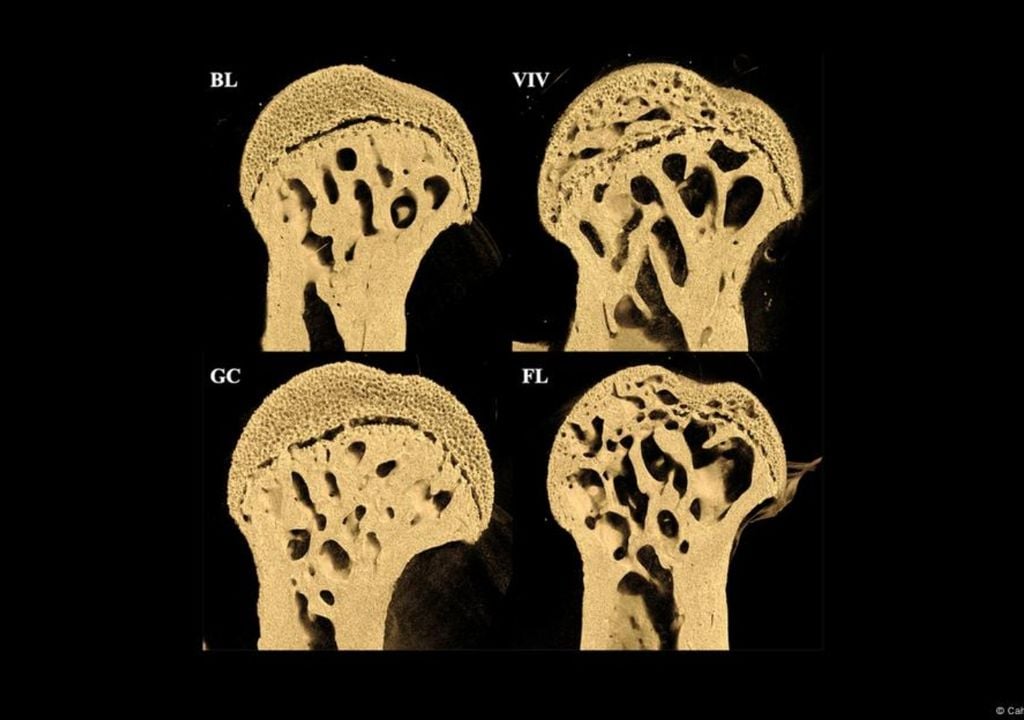

Os resultados surpreenderam os cientistas: ao fim de 37 dias, os ossos dos animais apresentavam alterações estruturais impressionantes. Descobriram que os ossos que normalmente suportam peso — como os fémures — foram os mais afetados.

Após pouco mais de um mês em órbita, os investigadores detetaram uma degradação óssea acentuada nas patas traseiras dos roedores, com grandes cavidades a indicar perda de densidade mineral.

Uns ossos com buracos, outros mais fortes

A deterioração não foi generalizada, o que descartou a radiação cósmica como causa primária. Em vez disso, a microgravidade parece alterar diretamente o equilíbrio do sistema esquelético.

A análise revelou um padrão curioso: enquanto os ossos de suporte sofreram uma deterioração acelerada, estruturas como a coluna lombar e o crânio permaneceram praticamente estáveis. De facto, algumas zonas do rosto e da mandíbula apresentaram um ligeiro aumento de densidade.

“A tomografia computorizada e as análises histológicas de ossos de ratinhos que voaram no espaço na Estação Espacial Internacional durante 37 dias na experiência Rodent Research-1 da NASA mostram uma perda óssea cortical e esponjosa significativa específica a ocorrer no fémur, mas não nas vértebras L2”, refere o artigo, publicado na revista PLOS ONE.